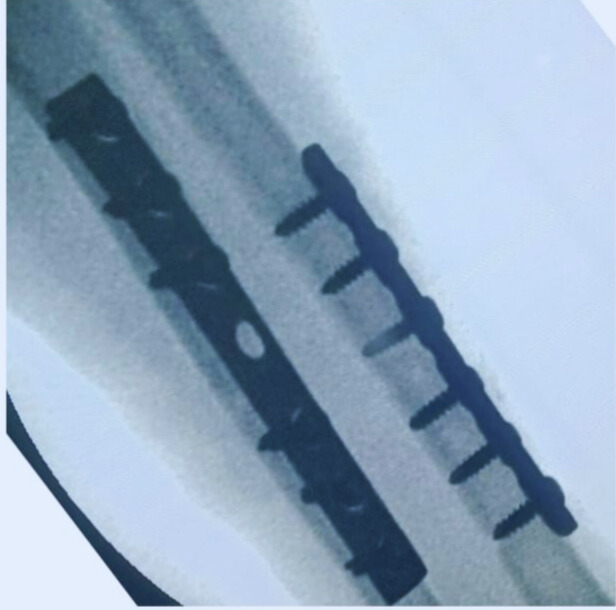

Postoperative image & Care:

The X-ray shows mid-shaft fixation of both forearm bones with plates, so post-operative care focuses on protecting the construct while promoting early controlled mobility. The limb is kept immobilized initially to reduce swelling and safeguard the fixation. Pain control and dressing care are maintained, while gentle finger, wrist, and elbow movements are started early to avoid stiffness. Progressive forearm rotation and strengthening exercises are introduced once initial healing is confirmed on follow-up X-rays. The patient should avoid lifting weight or applying torsional stress until radiographs show stable callus formation and advancing union.

The surgery was performed using high-quality implants and precision instruments from Samay Surgical. The fixation involved a Reconstruction Plate Straight D.C Hole 3.5mm (6-Hole) and a Narrow Compression DCP Plate 4.5mm (7-Hole), both engineered by Samay Surgical for optimal contouring and strong mid-shaft stabilization.